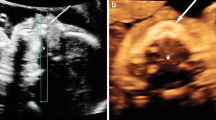

The mean quality of each standard view for 2-D and 3-D acquisitions is also presented in Table 5. The 3-D studies produced higher quality images for all coronal plane views, with an example demonstrated in Fig. 4 reaching statistical significance for the frontal horns (P=0.04) and third ventricle and Sylvian (P=0.03) views. The 2-D studies were of higher quality for the sagittal plane views, reaching statistical significance for the caudothalamic groove view (P=0.02) (Fig. 5).

A 25-day-old girl with a normal cranial ultrasound (US). a Two-dimensional (D) US coronal view of the temporal uncus and Sylvian fissure. All three observers rated this view quality ‘adequate’. b Coronal reconstruction of the 3-D volumetric US dataset of the temporal uncus and Sylvian fissure view. Two observers rated this view quality ‘excellent’, and one ‘good’

An 18-day-old girl with a normal cranial ultrasound (US). a Two-dimensional (D) US sagittal view of the right caudothalamic groove. One observer rated this view quality as ‘good’, and two ‘adequate’. b Sagittal reconstruction of the 3-D volumetric US dataset of the right caudothalamic groove view. Note the pivot point used for 3-D manipulation and reconstruction (caliper). The image also demonstrates the smaller near field view of the 3-D acquisition. One observer rated this view quality as ‘good’, one ‘adequate’, and one ‘poor’

A 14-day-old girl with hydrocephalus. a Two-dimensional (D) ultrasound (US) sagittal view of the right caudothalamic groove demonstrates hydrocephalus and increased periventricular echogenicity. One observer rated this view quality ‘poor’, and two ‘adequate’. b Sagittal reconstruction of the 3-D volumetric US dataset of the right caudothalamic groove view demonstrates the smaller near field view of the 3-D acquisition. Note the pivot point used for 3-D manipulation and reconstruction (caliper). One observer rated this view quality ‘adequate’, and two ‘poor’

A further limitation is that although efforts were made to blind the readers to the nature of the US acquisition, there is a clear difference between the images of a 2-D acquired view and a view reconstructed from a 3-D volume, with a narrower near field in the 3-D view, demonstrated in Figs. 4, 5, and 6. Therefore, the readers were able to infer the mode of acquisition.